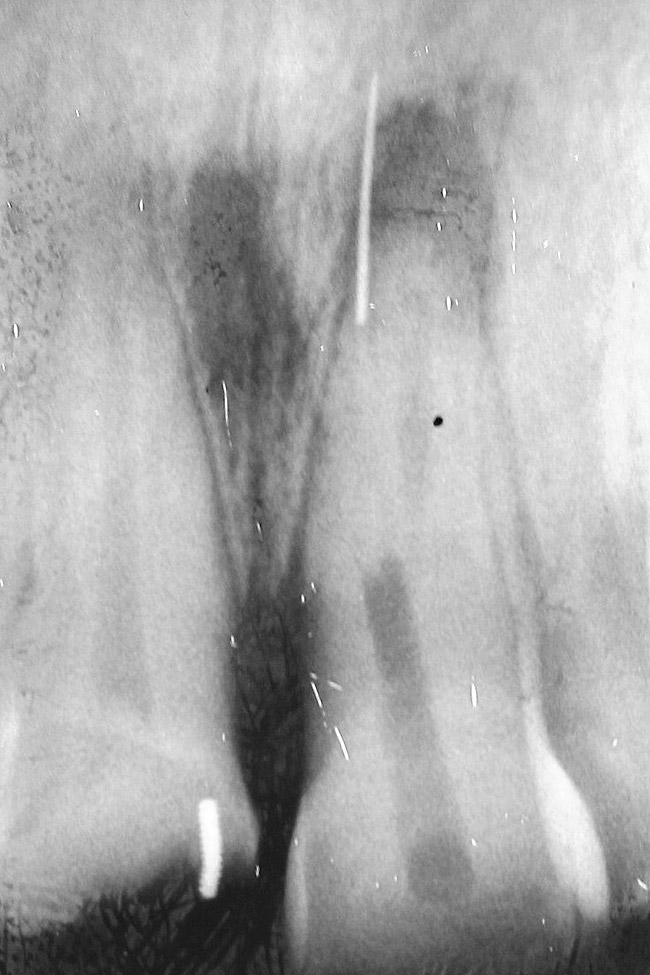

Figure 2  A radiograph finds no pulp chamber in the slightly dark central incisor and a silver point on the darkest lateral incisor. A titrated approach to bleaching was needed using individual tooth treatments.

Figure 2